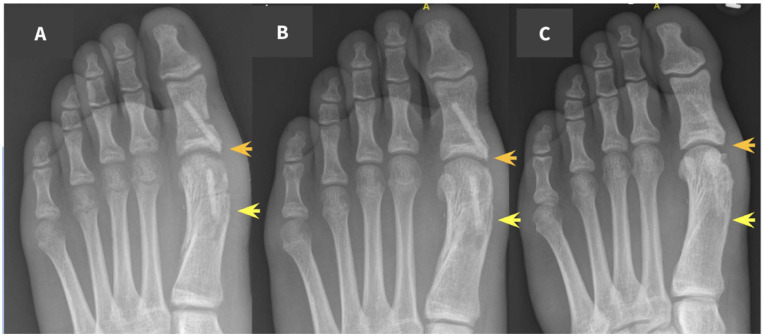

La serie incluye diferentes procedimientos del miembro inferior pediátrico. Entre los enumerados en el artículo:

- Chevron-Akin (hallux valgus juvenil)

- Artrodesis metatarsofalángica (MTF) / interfalángica (IF)